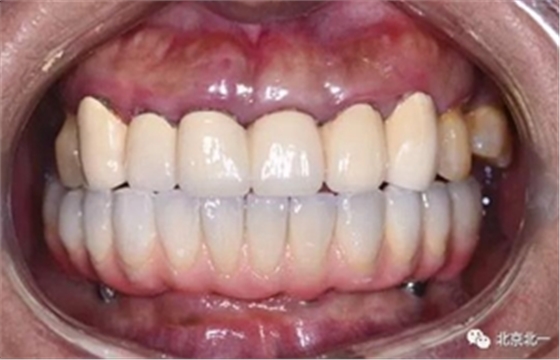

圖十九:永久修復(fù)完成

圖二十:永久修復(fù)咬合關(guān)系

圖二十五:口內(nèi)照。